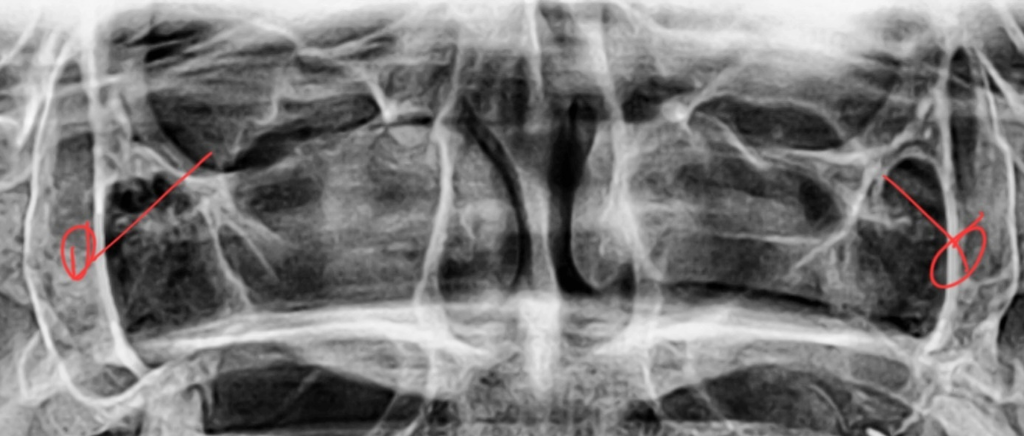

상악동 옆에 이게 뭔가요? 뼈? 근육?

뼈인가요? 근육인가요? 이름이 뭔지 알수 있나요??

치과 파노라마 사진 일부분 자른거 입니다

현재 사진에는 근육은 관찰되지 않습니다. 말씀하신 부위는 상악동의 상연 및 안와의 하연일 가능성이 높아 보입니다. 해당 뼈가 없다면 상악동과 다른 부위가 개통되어 염증 등이 쉽게 생길 수 있으며 위쪽 감염의 통로가 될 수 있습니다. 다만 현재 상태에서는 파노라마 뿐만 아니아 CT 자료도 필요합니다.

엑스레이에서 보이는 저 부분은 뼈입니다. 사진이 정확하지 않지만 대충 저위치는 외측익상판이라는 구조물 같습니다.